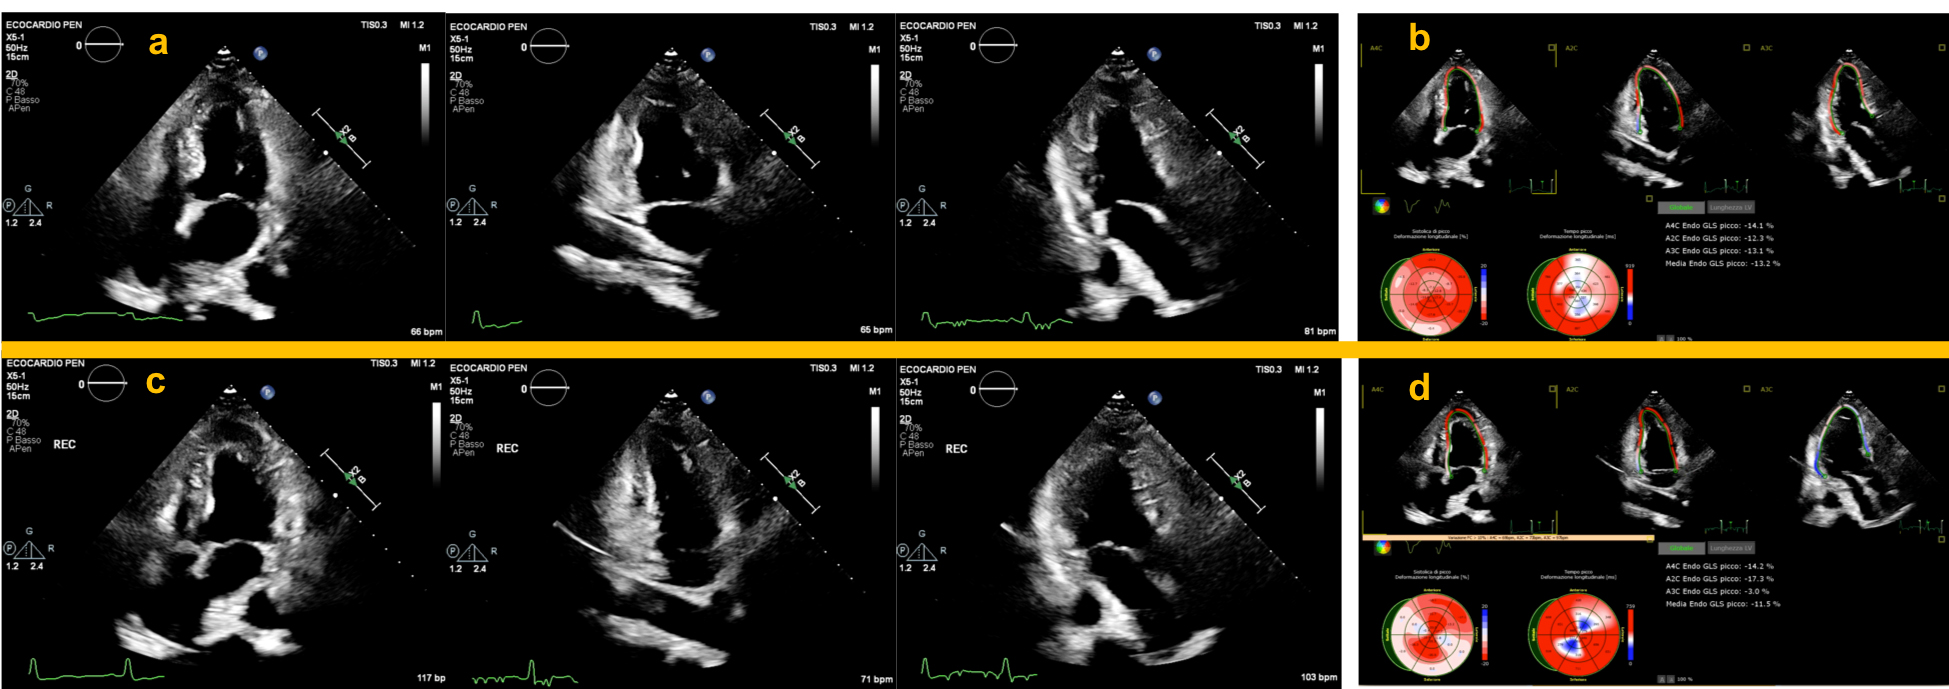

Fig. 3.Application of strain analysis during ESE in patients with severe obstruction of the LAD and RCA. Upper panels show normal resting apical chambers view during end-systole (a), and strain analysis performed simultaneously, showing a significant reduction in the septal and inferior segments (b). Lower panels: immediate post-exercise apical chambers view depicting a normal WM response with decreased LVESV (c). Strain analysis performed immediately post-exercise showed a well-defined segmental worsening in the LAD and RCA territory compared to baseline values (d). Also note the significant decrease in GLS which points to an increased risk of multivessel coronary heart disease. ESE, exercise stress echocardiography; LAD, left anterior descending coronary artery; RCA, right coronary artery; WM, left ventricular wall motion; LVESV, left ventricular end-systolic volume; GLS, global left ventricular longitudinal strain.